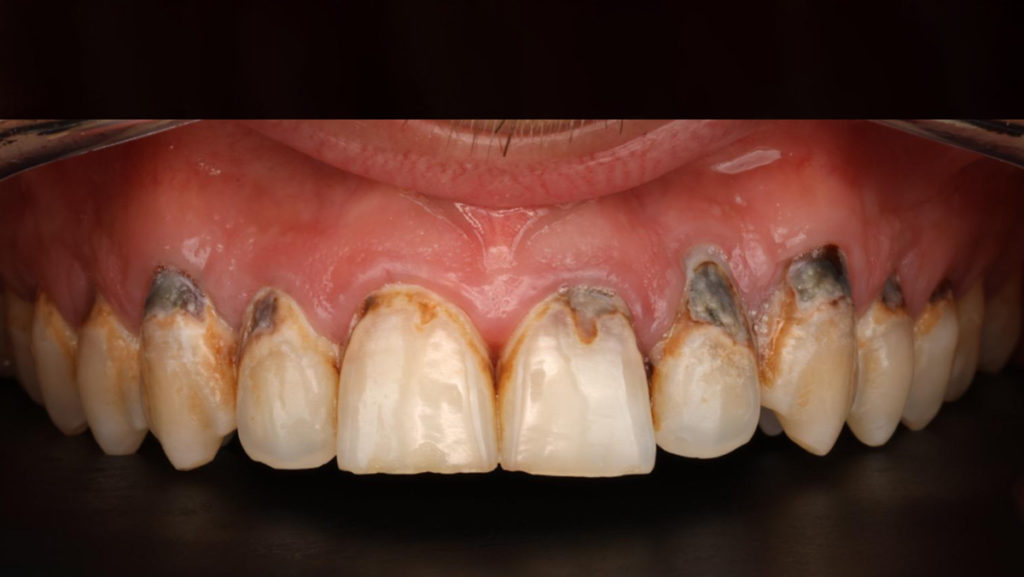

En esta imagen se muestra cómo el azúcar y el ácido de estas bebidas afecta a los dientes.